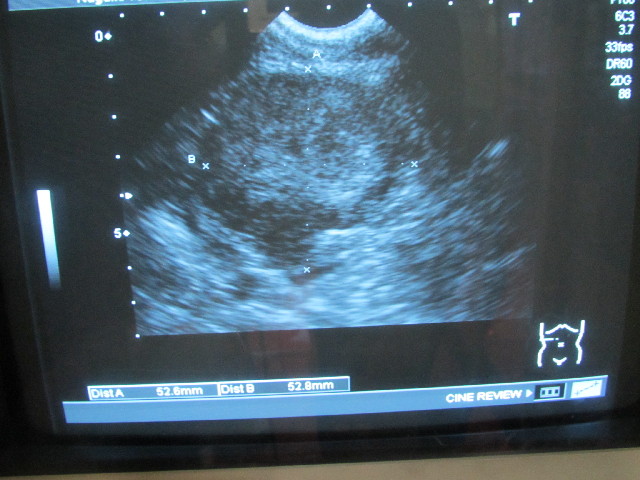

今日はべべちゃん腎臓の移行上皮癌(バブちゃん)の大きさを調べるエコー検査の日でした。

最大直径は2週間前と同じ約53ミリ(52.6×52.8mm)(^-^)v

発見当初は大きくなるのが速かったけど、ここ1〜2ケ月がグッと大きくなるペースが落ちました(^-^)v

2月27日からは約1mmしか大きくなっていないということ!

腎臓の下に(たしか)下大静脈が通っているが、今のところ圧迫されていない。

すごく大きくなって下大静脈が押しつぶされるとうっ血して、消化管浮腫や、吐き気、下痢等が起こるかもしれないが、このぶんならそんなふうにはならない。

このままほんの少しずつしか大きくならなければ、そんなになるまでにはかなり長い時間(1〜2年)かかるとのこと。